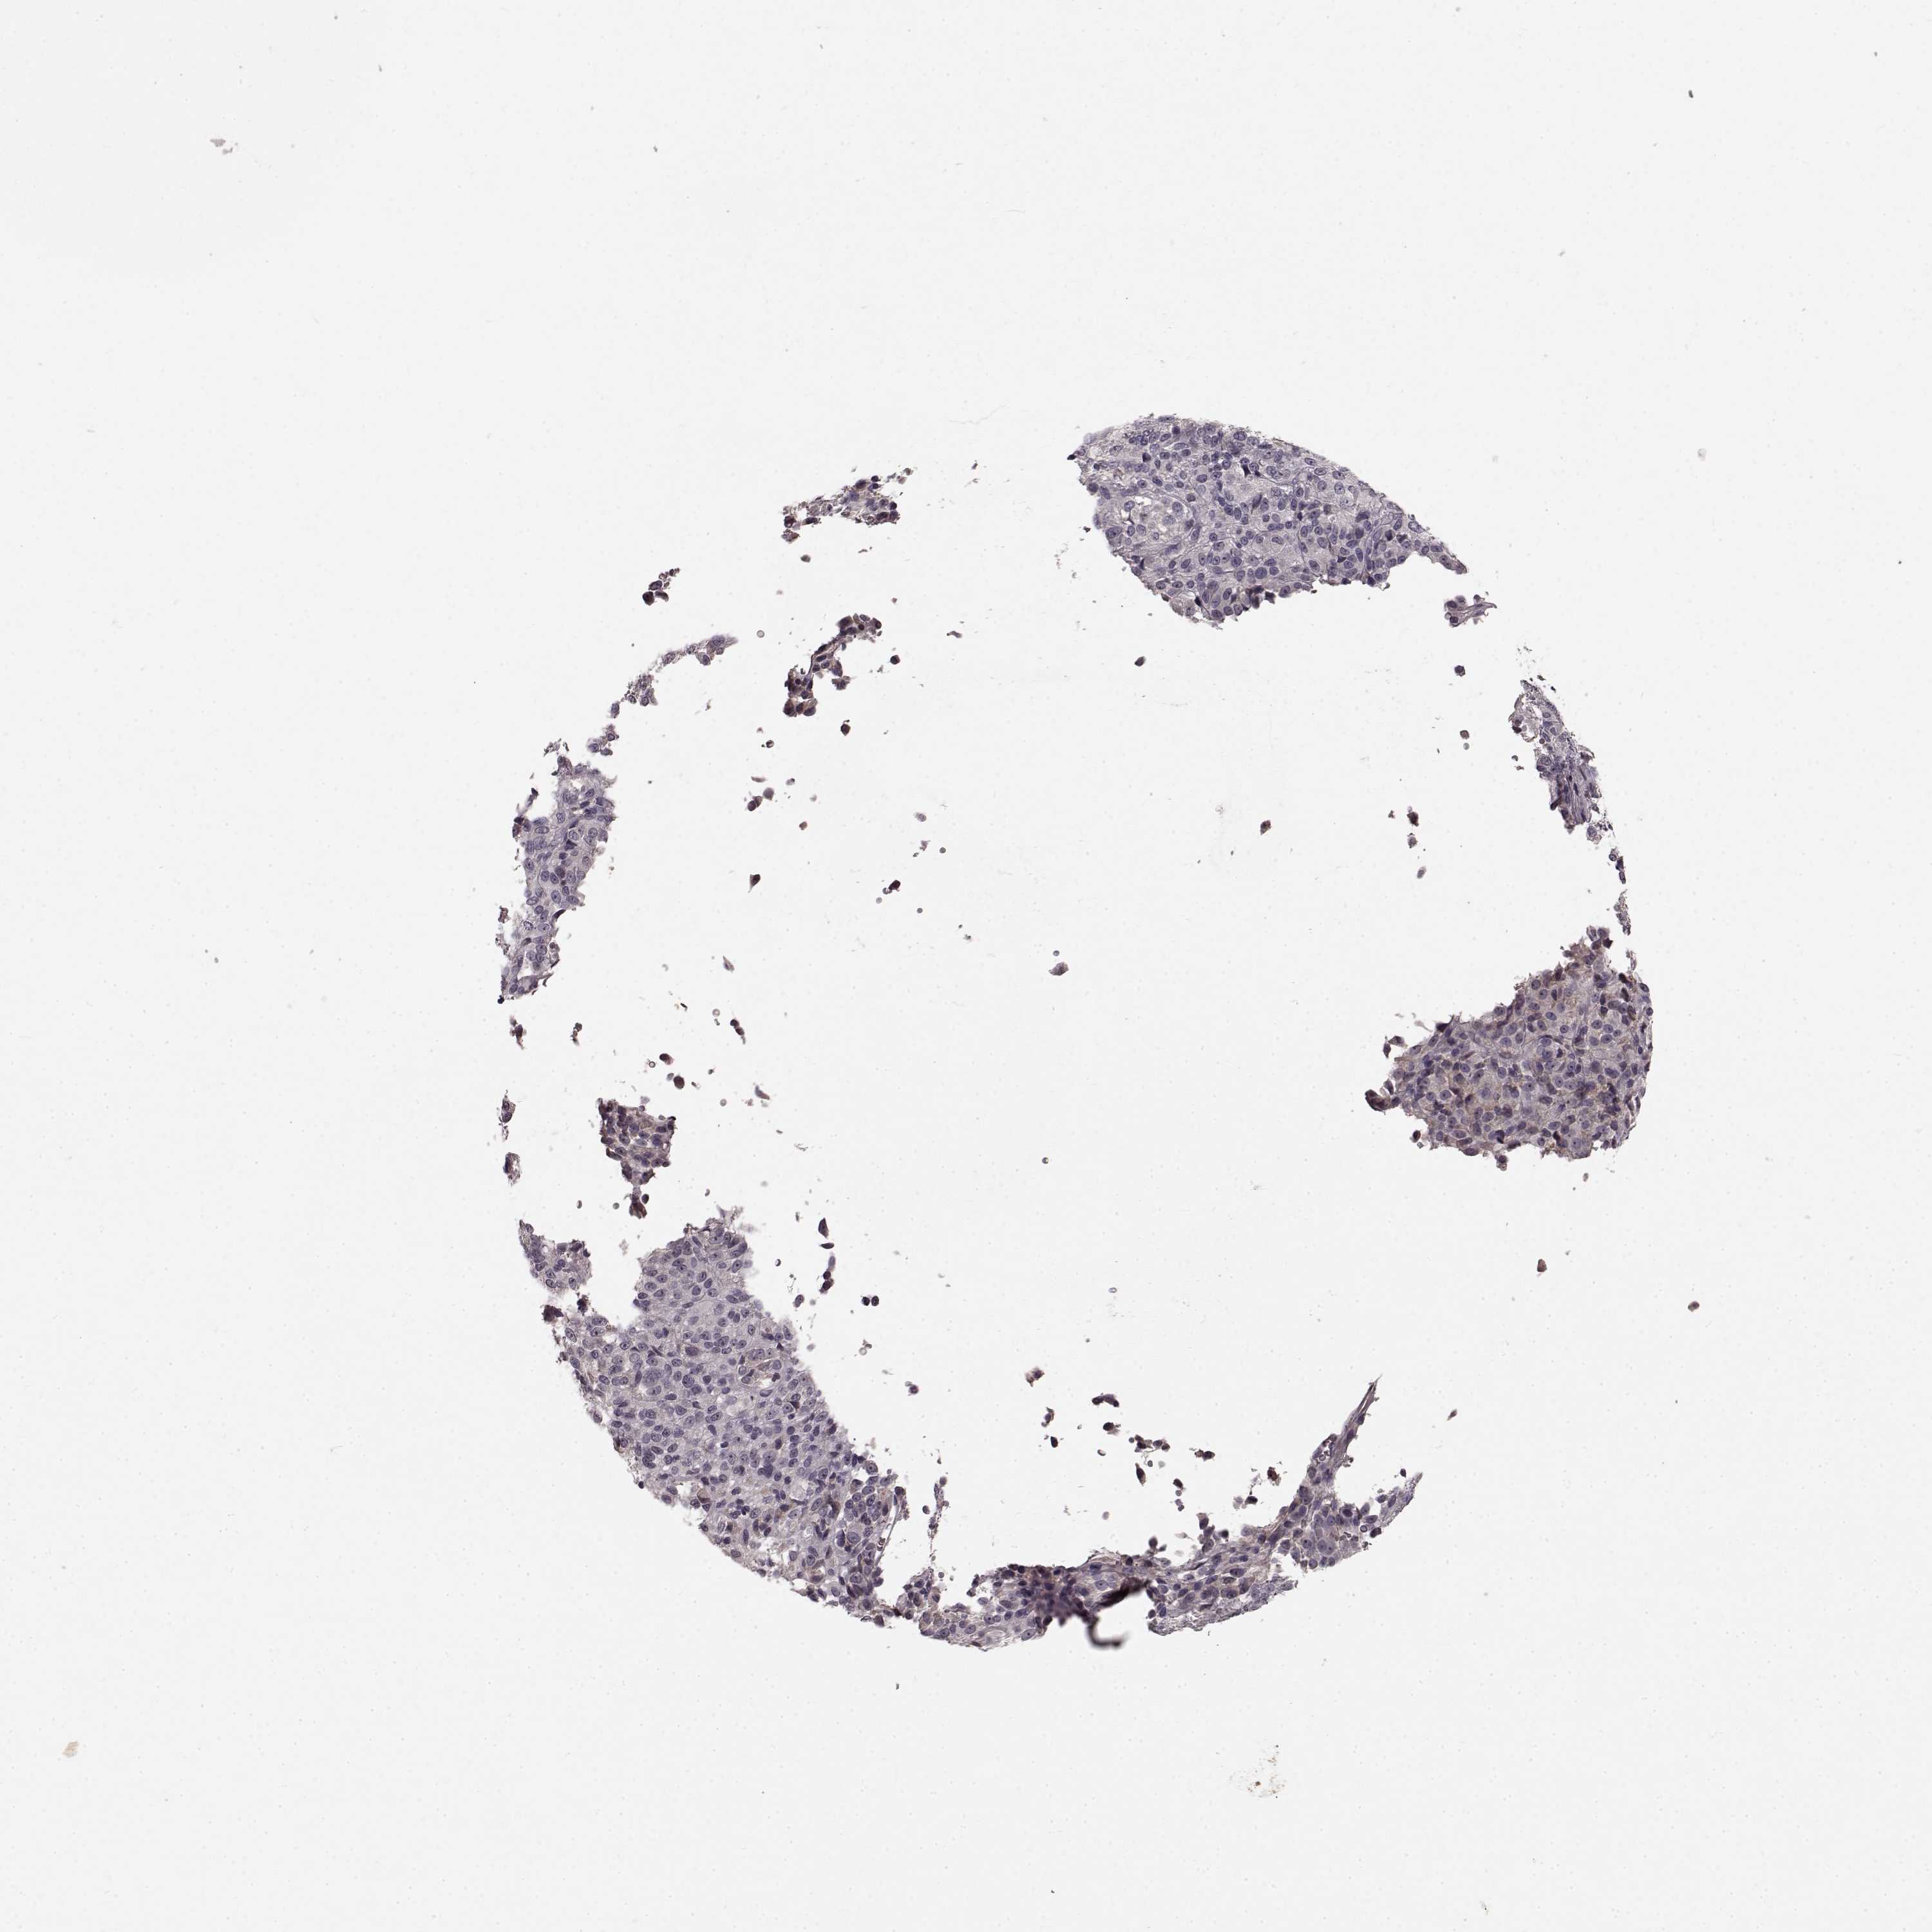

MELANOMA - Protein expressioni

A mouse-over function shows sample information and annotation data. Click on an image to view it in a full screen mode. Samples can be filtered based on level of antibody staining by selecting one or several of the following categories: high, medium, low and not detected. The assay and annotation is described here.

Note that samples used for immunohistochemistry by the Human Protein Atlas do not correspond to samples in the TCGA dataset.

Antibody stainingi

Antibody staining in the annotated cell types in the current human tissue is reported as not detected, low, medium, or high, based on conventional immunohistochemistry profiling in selected tissues. This score is based on the combination of the staining intensity and fraction of stained cells.

Each image is clickable and will lead to virtual microscopy that enables deeper exploration of all samples and also displays staining intensity scores, fraction scores and subcellular localization as well as patient and tissue information for each sample.

Antibody HPA067812

Antibody HPA071461

Staining

High

Medium

Low

Not detected

Intensity

Strong

Moderate

Weak

Negative

Quantity

>75%

75%-25%

<25%

None

Location

Nuclear

Cytoplasmic/membranous

Cytoplasmic/membranous,nuclear

Malignant melanoma, NOS

Malignant melanoma, Metastatic site